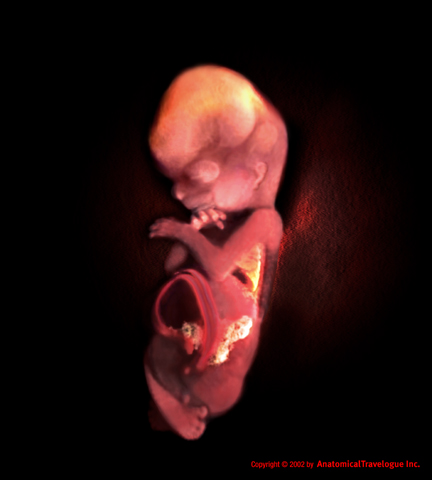

State per raggiungere un importante traguardo, la fine del primo trimestre. Il vostro bambino ora pesa quasi 14 grammi. Può aprire la bocca e piegare le dita dei piedi e delle mani, sulle quali piccole unghie hanno iniziato a crescere. Lo sviluppo del cervello è a buon punto poiché le cellule nervose fetali si moltiplicano rapidamente e le sinapsi iniziano a svilupparsi.

La dodicesima settimana di gravidanza